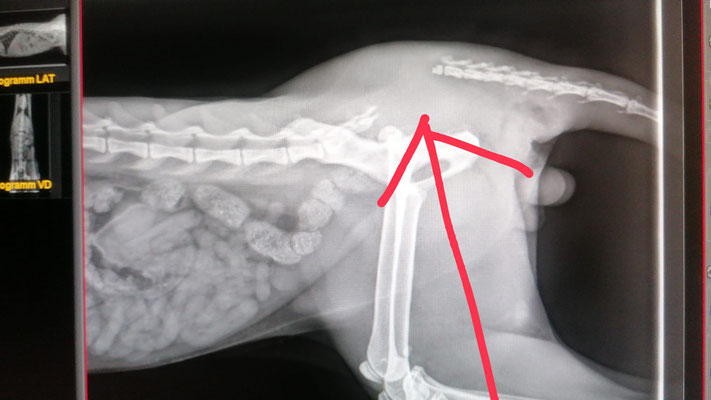

Rudi hatte 2024 vermutlich einen schweren Autounfall mit einem Hüftgelenksausbruch und einem Schwanzabriss. Normalerweise können Katzen mit einem Schwanzabriss von selbst keinen Urin / Kot mehr absetzen. Wie durch ein Wunder kann Rudi beides aber problemlos. Den Schwanz kann er allerdings nicht mehr einsetzen, er hängt also einfach locker nach unten. Rudi war anfangs sehr scheu, ein kleiner "Fauchi". Er hat sich aber sehr schnell an die Helferlein vom Katzenhaus gewöhnt und ist jetzt eine echte Schmusebacke.